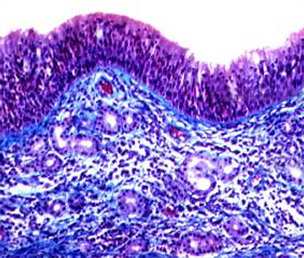

过敏性鼻炎即变应性鼻炎,是指特应性个体接触变应原后,主要由IgE介导的介质(主要是组胺)释放,并有多种免疫活性细胞和细胞因子等参与的鼻黏膜非感染性炎性疾病。其发生的必要条件有3个:特异性抗原即引起机体免疫反应的物质;特应性个体即所谓个体差异、过敏体质;特异性抗原与特应型个体二者相遇。变应性鼻炎是一个全球性健康问题,可导致许多疾病和劳动力丧失。